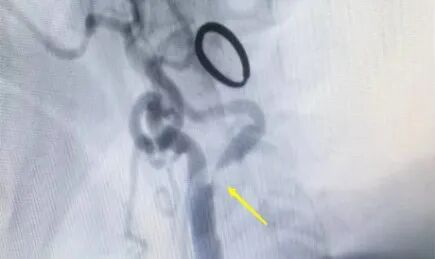

術(shù)前重度狹窄的頸動脈,幾乎無法顯影

70歲高齡的陳奶奶因頭暈、乏力不適,入住惠州三院神經(jīng)醫(yī)學中心神經(jīng)內(nèi)科,被確診為腦梗死、頸內(nèi)動脈狹窄(狹窄程度高達70%-99%)!她之所以產(chǎn)生頭暈、乏力等癥狀,正是頸內(nèi)動脈狹窄導致腦部供血不足所致。治療團隊充分評估,結(jié)合患者的病情和治療意愿,為其制定了頸內(nèi)動脈內(nèi)膜剝脫術(shù)的治療方案,患者隨即轉(zhuǎn)入神經(jīng)外科。

術(shù)后顯示血管充盈